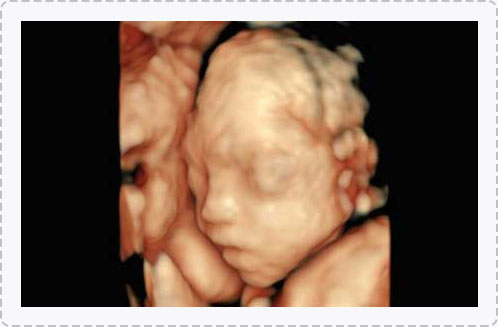

徐桂芳主任医师

超声科主任

从事妇产科超声影像工作多年

广州花都时代妇产医院超声科主任

专业擅长

妇科疾病及胎儿附属物的检查,对胎儿颜色、面、各器官的发育情况、胎儿在母体里的状态、胎儿畸形(如唇裂、腭裂、骨骼发育异常、心血管畸形等)能准确诊断。